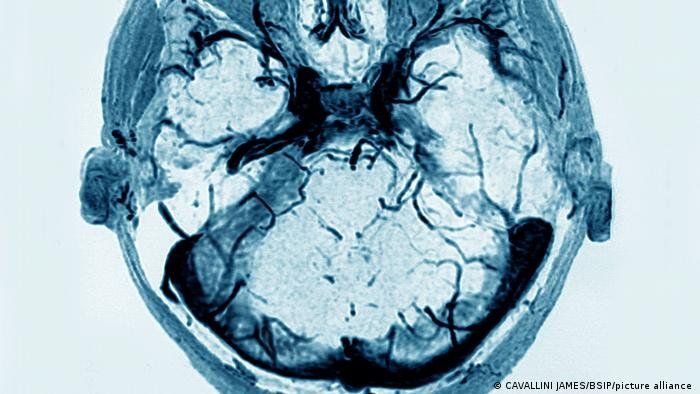

Fueron observados "nueve casos de trombosis, atípicas por su localización (mayoría cerebral, pero también digestiva) asociadas a una trombocitopenia o a problemas de coagulación", seis más en relación con la semana precedente, informó la ASNM.